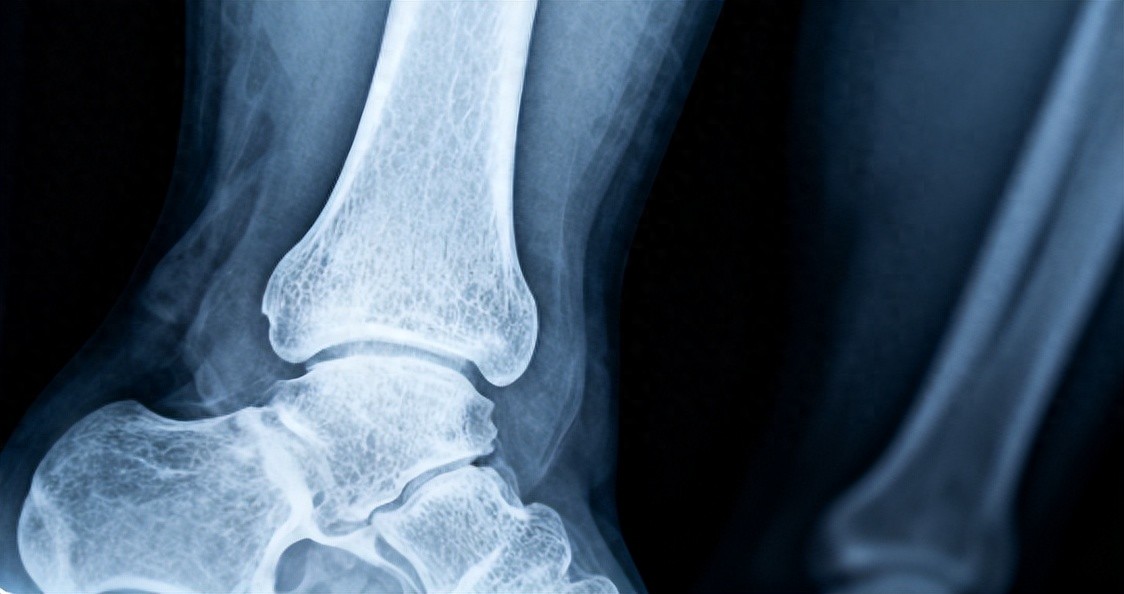

走路:对关节的好处有哪些?1.走路作为低冲击、高效能的运动,能有效促进血液循环。它可加速关节周边血液流动,优化营养供给,助力关节软骨维持弹性,对关节健康大有益处。正如古人云,“走千里路,胜读万卷书”,走路不仅能锻炼身体,还能缓解压力,释放紧张情绪。对于长期坐着或站立的工作者,适量的走路能帮助减轻关节的负担。

2.增强关节的灵活性长期的关节疼痛,往往与关节周围的肌肉弱化、关节僵硬有关。步行,作为一种简便易行的运动方式,能够卓有成效地锻炼腿部肌群。在一步一步的前行中,腿部肌肉得到充分刺激,进而增强肌肉力量,助力身体康健。同时,它能扩大关节的活动幅度,促进关节灵活运转,进而显著减轻关节的僵硬不适之感。尤其是对于膝关节,规律的散步能增强膝盖周围的肌肉力量,减轻膝盖的负担,避免骨关节炎的加重。

但是,走路也不是适合所有人1.关节炎患者慎重尽管走路对大多数人有益,但对于患有严重关节炎的患者来说,剧烈走路或走得过久可能会加重病情。特别是那些膝关节、髋关节已经严重退化的人,长时间的行走可能会加重关节的磨损,导致更多的疼痛和不适。此类患者在开始走路前,应咨询医生,了解合适的运动量。